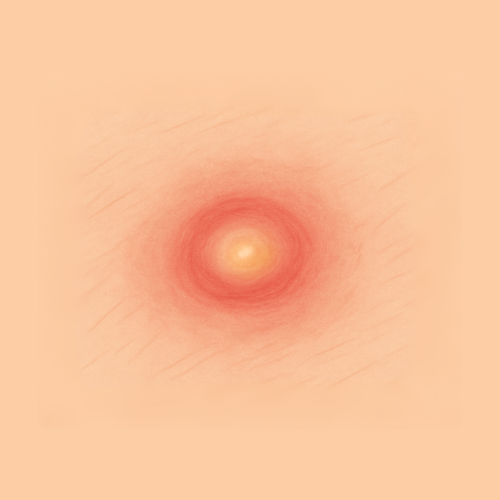

Find Relief by Symptom or Skin Concern

EMUAID is designed to relieve symptoms from over 100 difficult-to-treat conditions like eczema, psoriasis, nail fungus, hemorrhoids, shingles, acne, rashes, burns, cellulitis, and more. If it's red, itchy, cracked, painful, or inflamed- EMUAID may help.